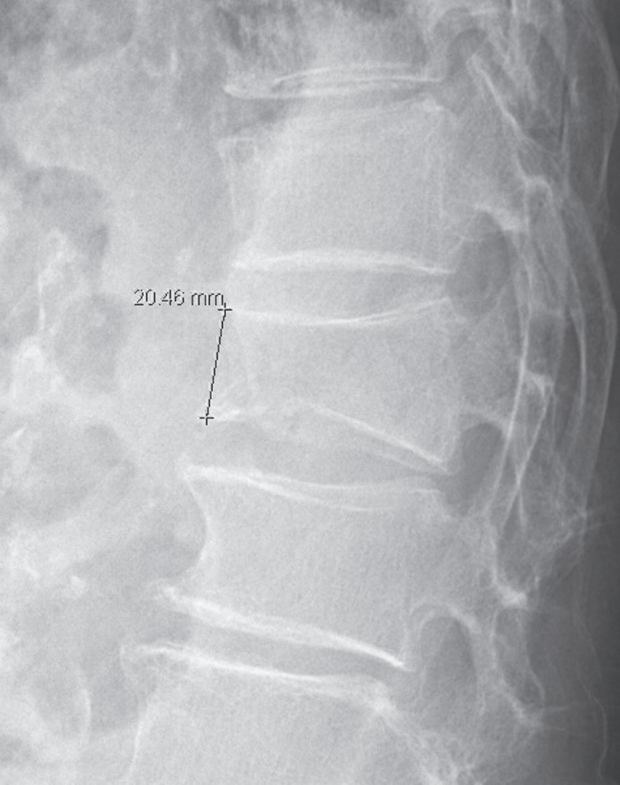

Clinical evaluations were performed at baseline, 1 month, and 3 months after treatment. Pain and disability were assessed using the Visual Analogue Scale (VAS) and the Oswestry Disability Index (ODI), both validated and widely used tools in spinal research. Radiographic assessment included measurement of anterior vertebral body height on lateral spine radiographs obtained at each time point. The height was measured by drawing a perpendicular line from the superior endplate to the inferior endplate at the anterior margin of the fractured vertebral body, as illustrated in Fig. 1.

Fig. 1.

Measurement of anterior vertebral body height.

Fig. 1. Measurement of anterior vertebral body height.